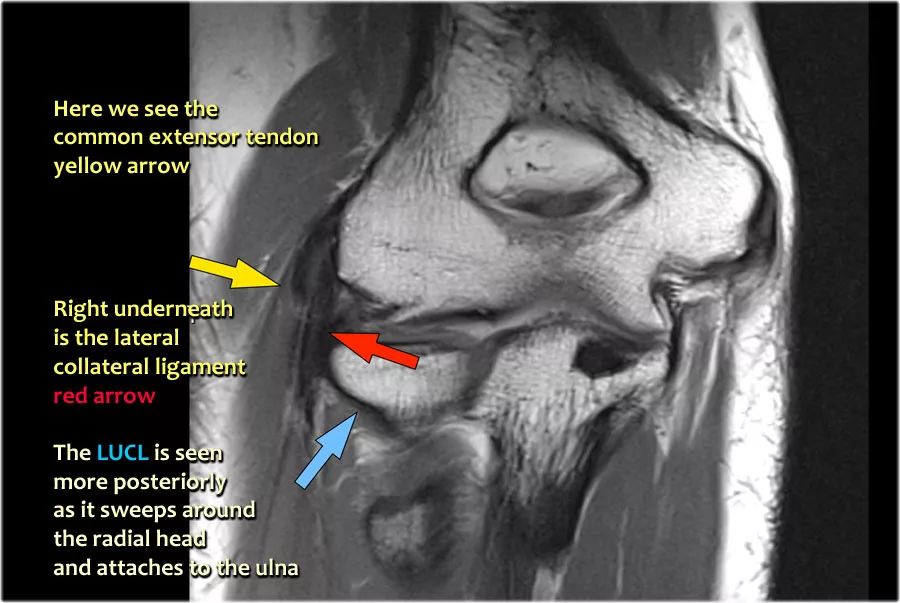

当您寻找桡侧副韧带时,首先要尝试识别常见的伸肌腱,因为在它下面你会发现桡侧副韧带(黄色箭头)。

当你向后走时,你会看到LUCL--侧面尺侧副韧带,它在桡骨头后面扫过(白色箭头)。环形韧带通常难以与RCL区分开,但有时可以在矢状MR-关节造影上识别。

我们可以从连续的冠状位MRI图像观察。

常见的伸肌腱起源于外上髁。在T1W图像上,肌腱应具有低信号强度(黄色箭头)。